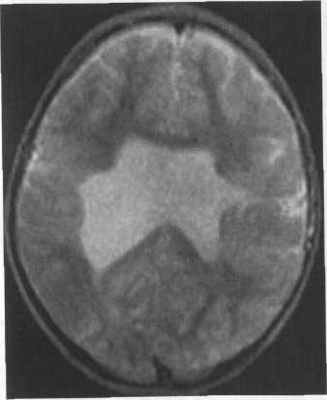

Субкортикальная групповая гетеротопия («двойная кора»):

(а) Аксиальный срез МРТ: широкие, непрерывные группы с таким же сигналом как от коры.

(б) Коронарный срез: в этом же случае имеется расширение желудочков преимущественно спереди.

Кроме того, была проведена магнитно-резонансная томография головного мозга (аппарат Hitachi Airis Mate 0,2 Тесла), согласно которой на аксиальных срезах определялись билатеральные лентовидные зоны, соответствующие серому веществу головного мозга, расположенные преимущественно субкортикально. Изгибы гетеротопированных слоев повторяли основную складчатость кортикальной поверхности. На коронарных срезах подтверждалось субкортикальное расположение гетеротопированных зон. В коре видимых диспластических изменений не отмечено. Таким образом, можно утверждать о наличии у пациентки МР-признаков билатеральной ламинарной гетеротопии серого вещества, что характерно для синдрома «двойной коры» (рис. 2).

Перивентрикулярная и субкортикальная гетеротопия как с изменением, так и без изменения строения коры проявляется узловой перивентрикулярной гетеротопией и скоплением серого вещества в субкортикальных отделах. Поражение в большинстве случаев одностороннее. Субкортикальное скопление серого вещества может приводить к локальной деформации борозд и утолщению коры (рис. 3.20).

Рис. 3.20. Перивентрикулярно-субкортикальная гетеротопия. МРТ.

а - IR ИП, аксиальная плоскость. Узлы гетеротопии располагаются вдоль стенки левого бокового желудочка и в субкортикальных отделах белого вещества. Между субкортикальными узлами сохраняются прослойки белого вещества. Поверхность коры деформирована.

б - Т2-ВИ, корональная плоскость. Субэпендимальные узлы вдаются в полость левого бокового желудочка, что делает его контуры волнистыми.